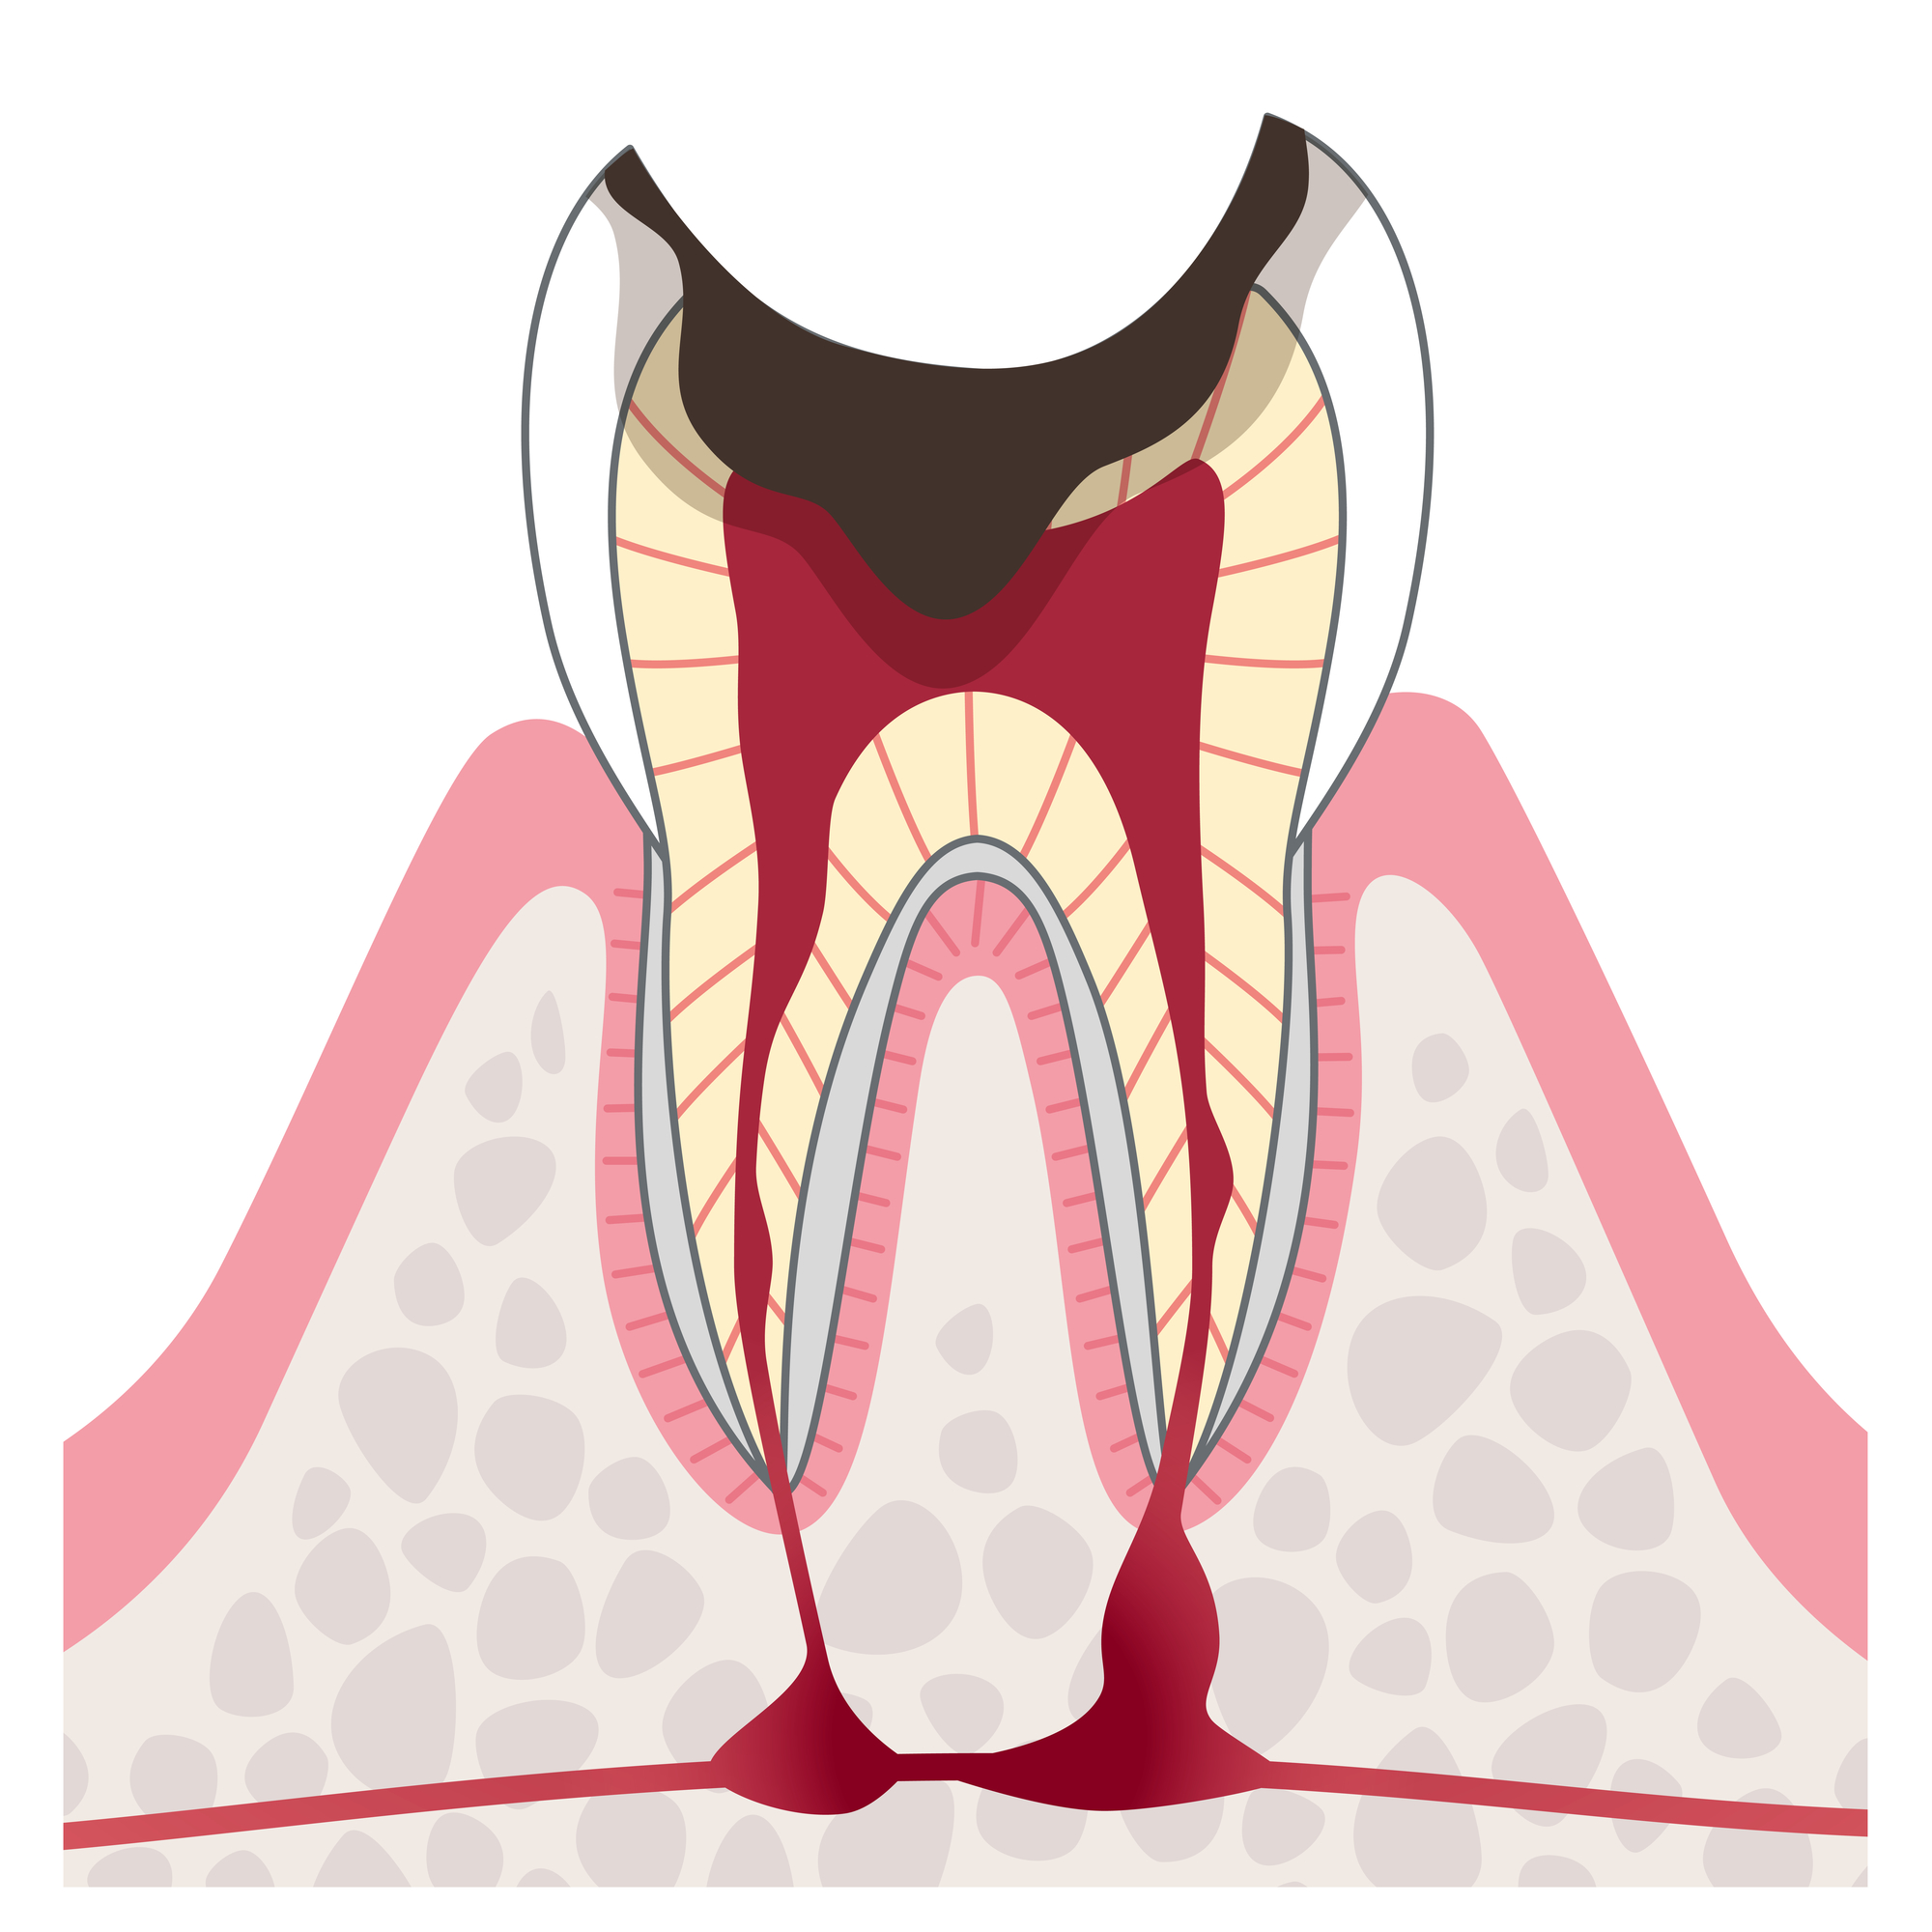

C4

治療方法

- インプラント

- 入れ歯

- ブリッジ